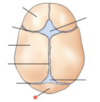

A

Forearm

15

Q

A

Phalanges

16

Q

A

Coracoid Process

17

Q

A

Head

18

Q

A